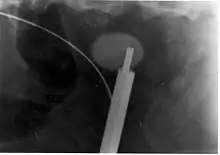

Lithotripsy

Extracorporeal shock wave lithotripsy (ESWL) is a noninvasive technique for the removal of kidney stones. Most ESWL is carried out when the stone is present near the renal pelvis. ESWL involves the use of a lithotriptor machine to deliver externally applied, focused, high-intensity pulses of ultrasonic energy to cause fragmentation of a stone over a period of around 30–60 minutes. Following its introduction in the United States in February 1984, ESWL was rapidly and widely accepted as a treatment alternative for renal and ureteral stones.[105] It is currently used in the treatment of uncomplicated stones located in the kidney and upper ureter, provided the aggregate stone burden (stone size and number) is less than 20 mm (0.8 in) and the anatomy of the involved kidney is normal.[106][107]

For a stone greater than 10 millimetres (0.39 in), ESWL may not help break the stone in one treatment; instead, two or three treatments may be needed. Some 80-85% of simple renal calculi can be effectively treated with ESWL.[7] A number of factors can influence its efficacy, including chemical composition of the stone, presence of anomalous renal anatomy and the specific location of the stone within the kidney, presence of hydronephrosis, body mass index, and distance of the stone from the surface of the skin.[105]